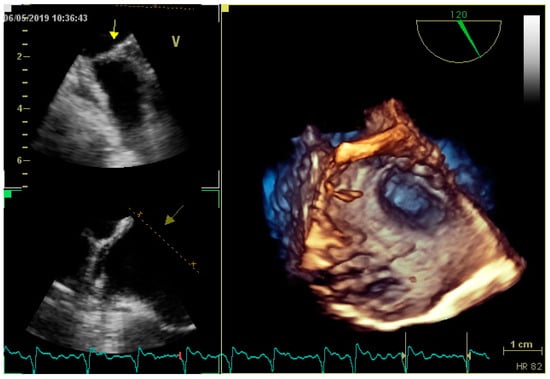

3.2. Transesophageal Echocardiography and Intracardiac Echocardiography